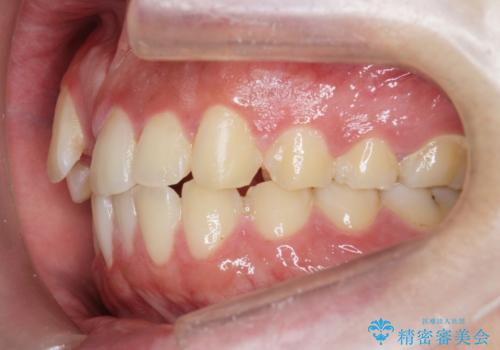

正中過剰埋伏歯で生じた前歯の審美障害 矯正治療での改善

- 前歯の見た目に悩まれて来院されました。

当初他院では、抜歯を行いセラミックブリッジを提案されていましたが、他の方法はないかと総合歯科治療を行う当院へと相談来院されました。

「時間がかかっても良いので、できれば歯を抜かずに矯正治療で治したい。」という強い希望があったので、矯正治療で歯並び・審美性の改善を計画します。

見た目、噛み合わせが大きく改善し、大変喜んでいただくことができました。